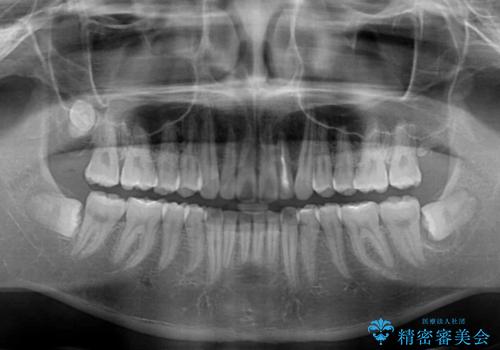

正面や横から見た印象が同じで用であっても、奥歯の咬み合わせが理想的であるかどうかによって、治療の難易度は大きく異なります。

こちらの方も難易度のやや高い状態で、2年以上の期間が予想されましたが、想定通りの2年強で治療を終えることができました。